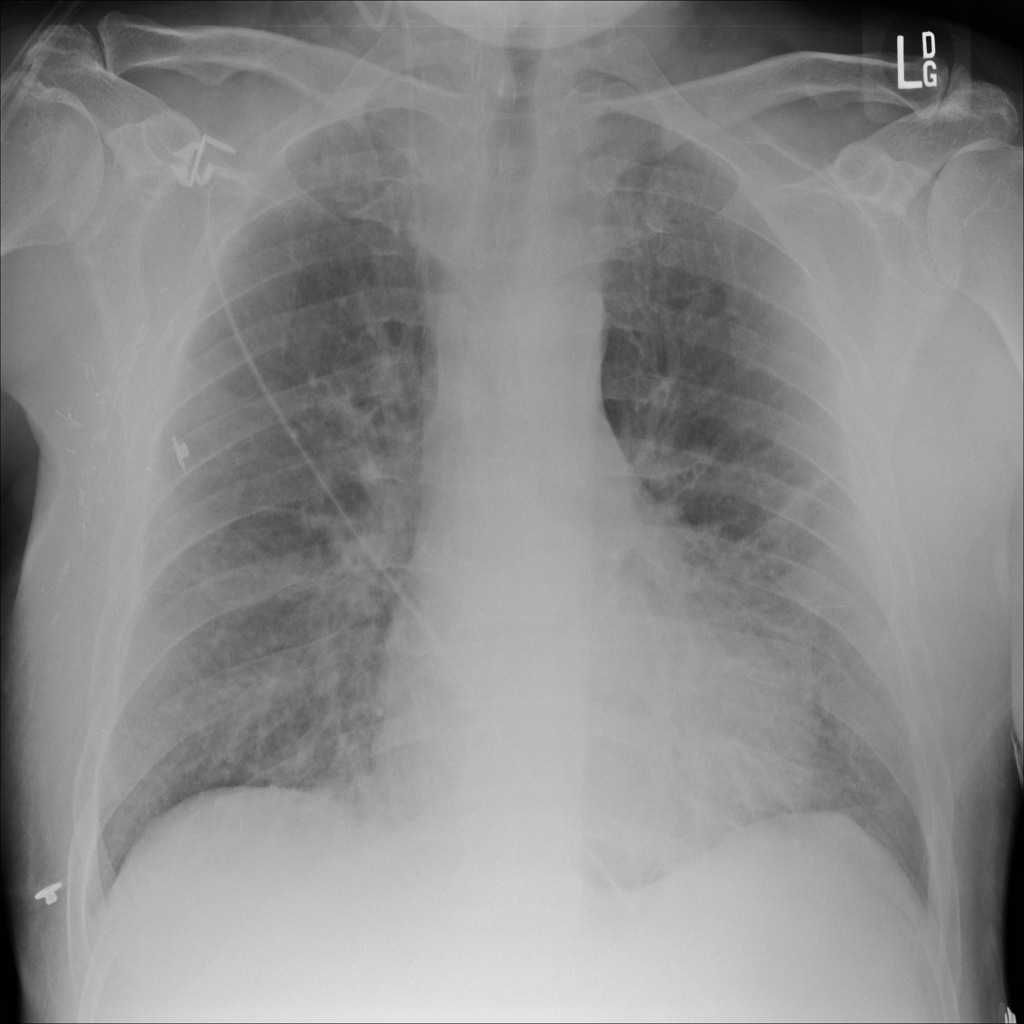

PAT-5B86 · IMG-009Edema

PAT-5B86 · IMG-009

PA